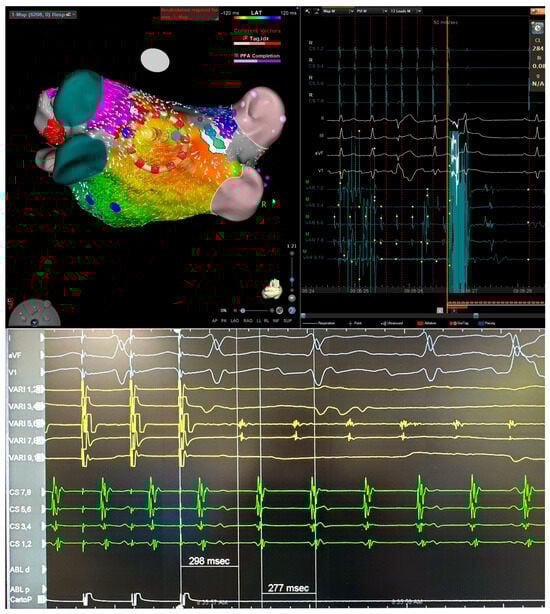

Figure 1.

Three-dimensional electroanatomical mapping of left atrium (left) and EGM (right) in a patient with persistent atrial fibrillation lasting 12 months. After pulmonary vein isolation and posterior wall isolation using PFA, roof line connecting the suprior veins was performed with conversion first to atypical atrial flutter (top) and then to sinus (bottom).

Figure 2.

Three-dimensional electroanatomical mapping of left atrium (left) and EGM (right) in a patient with atrial flutter. Entrainment mapping and activation mapping confirmed peri-mitral atrial flutter. Anterior mitral line from right superior pulmonary vein to mitral valve caused prolongation of cycle length (top). Roof line connecting the superior veins terminated the atrial flutter (bottom).